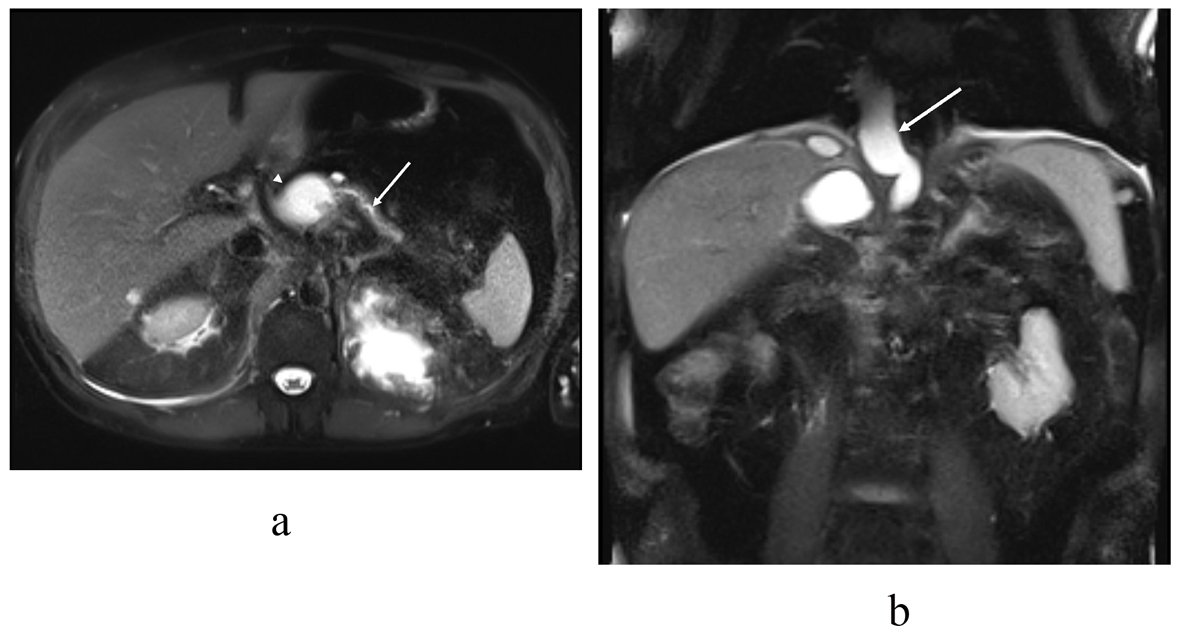

One month later, MRCP showed that the fluid collection was around the pancreas and the pancreatic duct was interrupted within the body of the pancreas (Fig. 3). The fluid collection protruded to the mediastinum but the lungs and pleurae were intact. The remaining fluid collection under the diaphragm was separated and deemed to be a chronic hematoma.

![]() Click for large image | Figure 3. T2 (haste) MRI in the (a) transaxial and (b) coronal plane demonstrates the distal pancreatic duct (arrow) communicating with the pancreatic body pseudocyst (arrowhead). In the coronal plane (b) a pseudocyst (arrow) extends through the hiatus opening to the mediastinum, similar to the previous CT scan. |